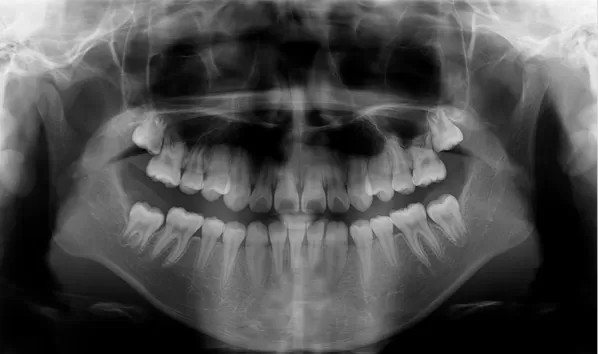

Rayons X avant le traitement

[Radiographie panoramique/Céphalogramme latéral]